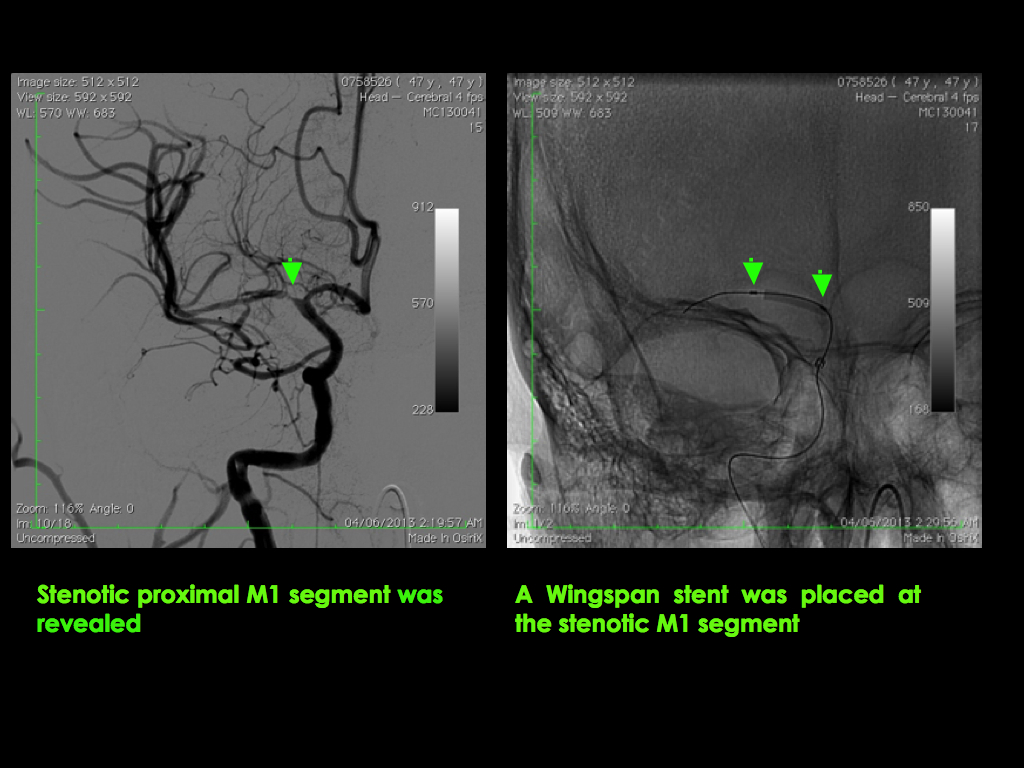

Sometimes if there is an underlying diseased and narrowed brain artery that is causing the stroke, our Stroke Neurosurgeons will implant a soft metallic stent for reconstructing the brain artery.